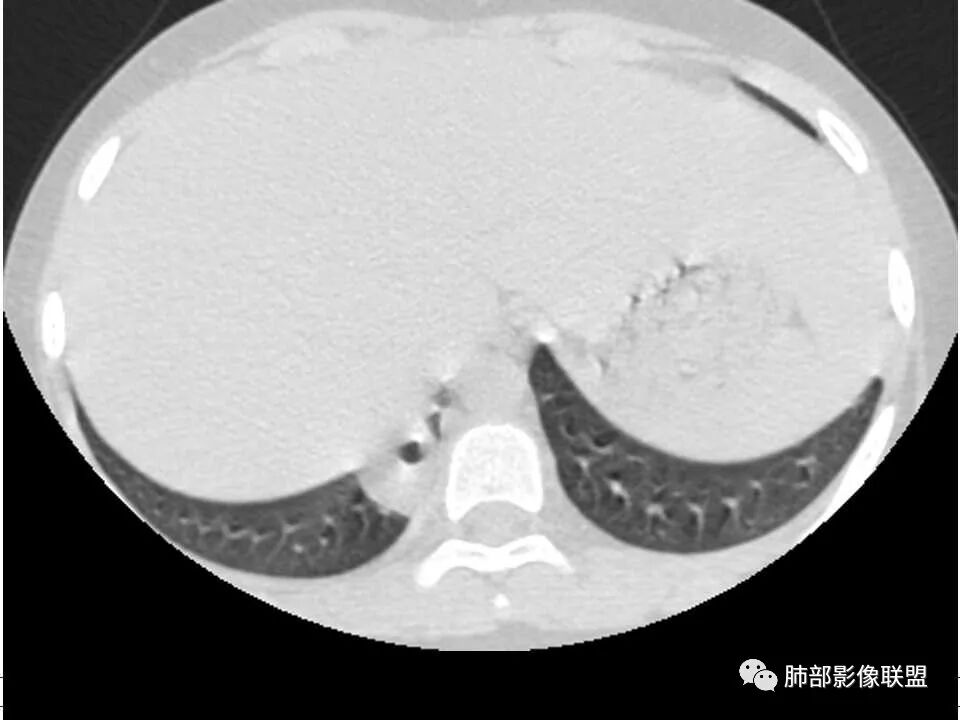

患者儿童,因右下肢疼痛伴肿胀14天就诊。病程中有发热及伴随症状。膝关节MRI提示右侧膝关节及右髌骨髁异常信号影,右膝髌上囊及关节腔内少量积液。胸部CT:双肺胸膜下多发结节影,部分结节空洞形成,且结节周围可见血管集束征。综合考虑血源性脓毒性肺栓塞、坏死性肺炎。右侧骨髓炎、血播性金葡菌肺炎,鉴别其他特殊感染及血管炎。

发热,下肢肿胀骨髓水肿,骨髓炎可能;双肺多发结节,部分空洞,左下肺胸膜下楔形阴影,考虑感染性病变,肺梗死;上腔静脉、奇静脉增宽,肝大,考虑股部深静脉拴子进入体循环及肺动脉,综上考虑下肢骨髓炎,深静脉脓毒栓子,肺部感染并肺栓塞

2.双肺多发片影,随机分布,多空洞或囊腔,胸膜下多楔形影,气道未见受累等等符合脓毒血症影像学表现,尤其是金葡。

1. 多发胸膜下外周结节、< 3 cm 的楔形影和滋养血管征 CT 表现;